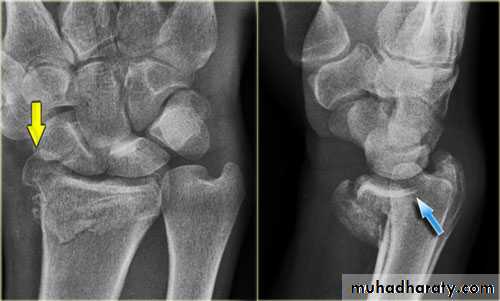

Upper limb

Fall on out stretched hand

xray